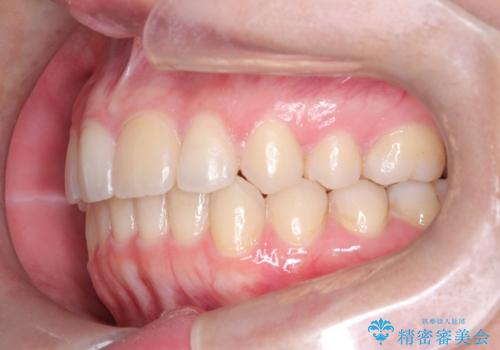

矯正後の後戻り インビザラインで改善

- 前歯のガタツキが気になると来院されました。

マウスピース矯正治療を選択しました。

前歯のガタツキを改善する治療法として、マウスピース矯正が適していることが多いです。

マウスピース矯正は、金属製のブラケットやワイヤーを使用せずに、透明なマウスピースを装着して歯を移動させる方法です。そのため、目立たず、痛みも少ないです。